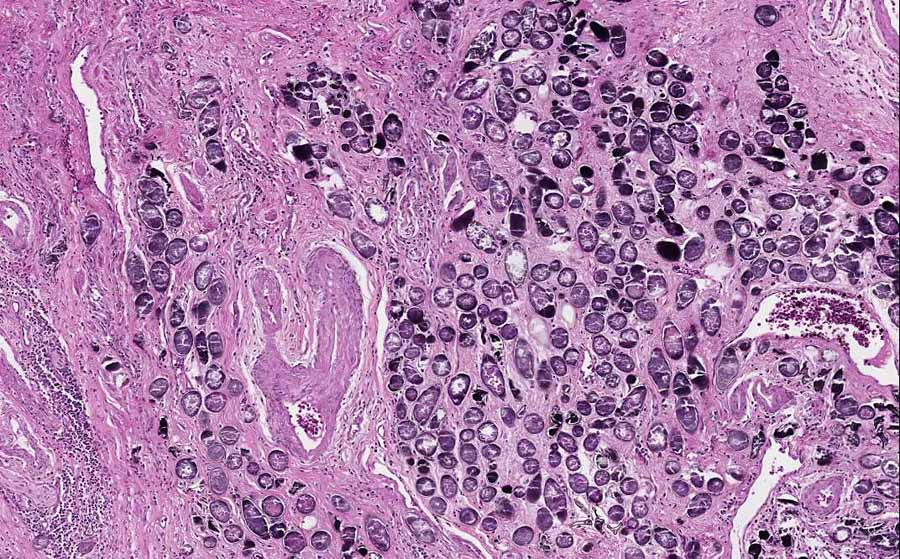

Hematoxylin & eosin

Area 2: The calcified eggs caused substantial fibrosis.

• This image is taken from the wall of a segment of colon. You can recognize the muscle layer. There are two disease processes. The first process is composed of nests of pleomorphic cells (Area 1). The pathologic features are that of a neoplasm of the colon. This is most likely the reason why this segment of colon was surgically removed. The pathology are suggestive of a carcinoid but no further information is provided in the archive.

• The more interesting lesion, however, is featured by numerous round to olive shaped structure with a calcified shell. These organisms are the calcified eggs of Schistosoma.